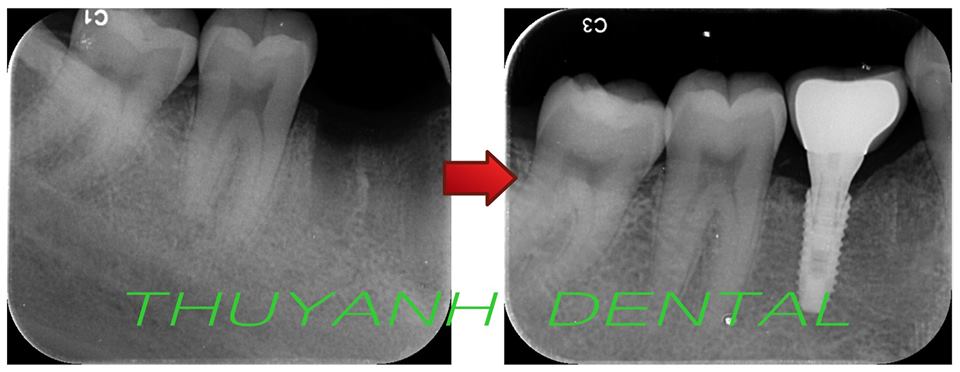

Phục hình răng sứ trên chân răng Implant:

Công việc phục hình răng trên chân răng Implant tương tự như khi bạn đi làm mão răng, hay cầu răngthông thường

Bác sĩ sẽ tư vấn bạn chọn phương pháp thích hợp nhất cho bệnh nhân. Có một số loại phục hình răng bạn có thể lựa chọn như răng sứ Cercon, răng sứ titan, răng sứ trên sườn hợp kim crom-coban…

Cấy implant thay thế 1 răng hàm bị mất do sâu răng cho bạn khách hàng nữ